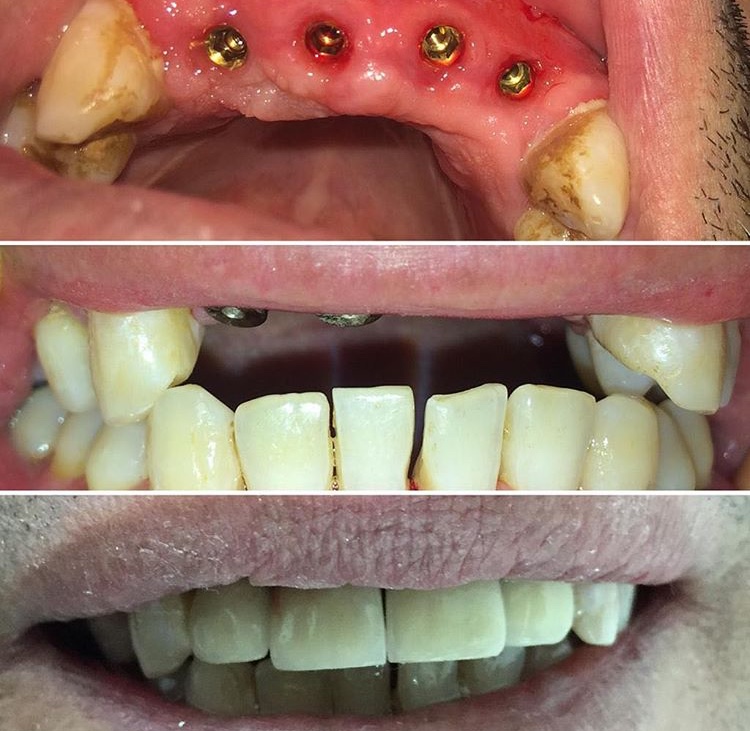

Implantes dentales y Rehabilitación sector anterior

La rehabilitación de implantes dentales es un método clínico que permite reemplazar dientes perdidos...